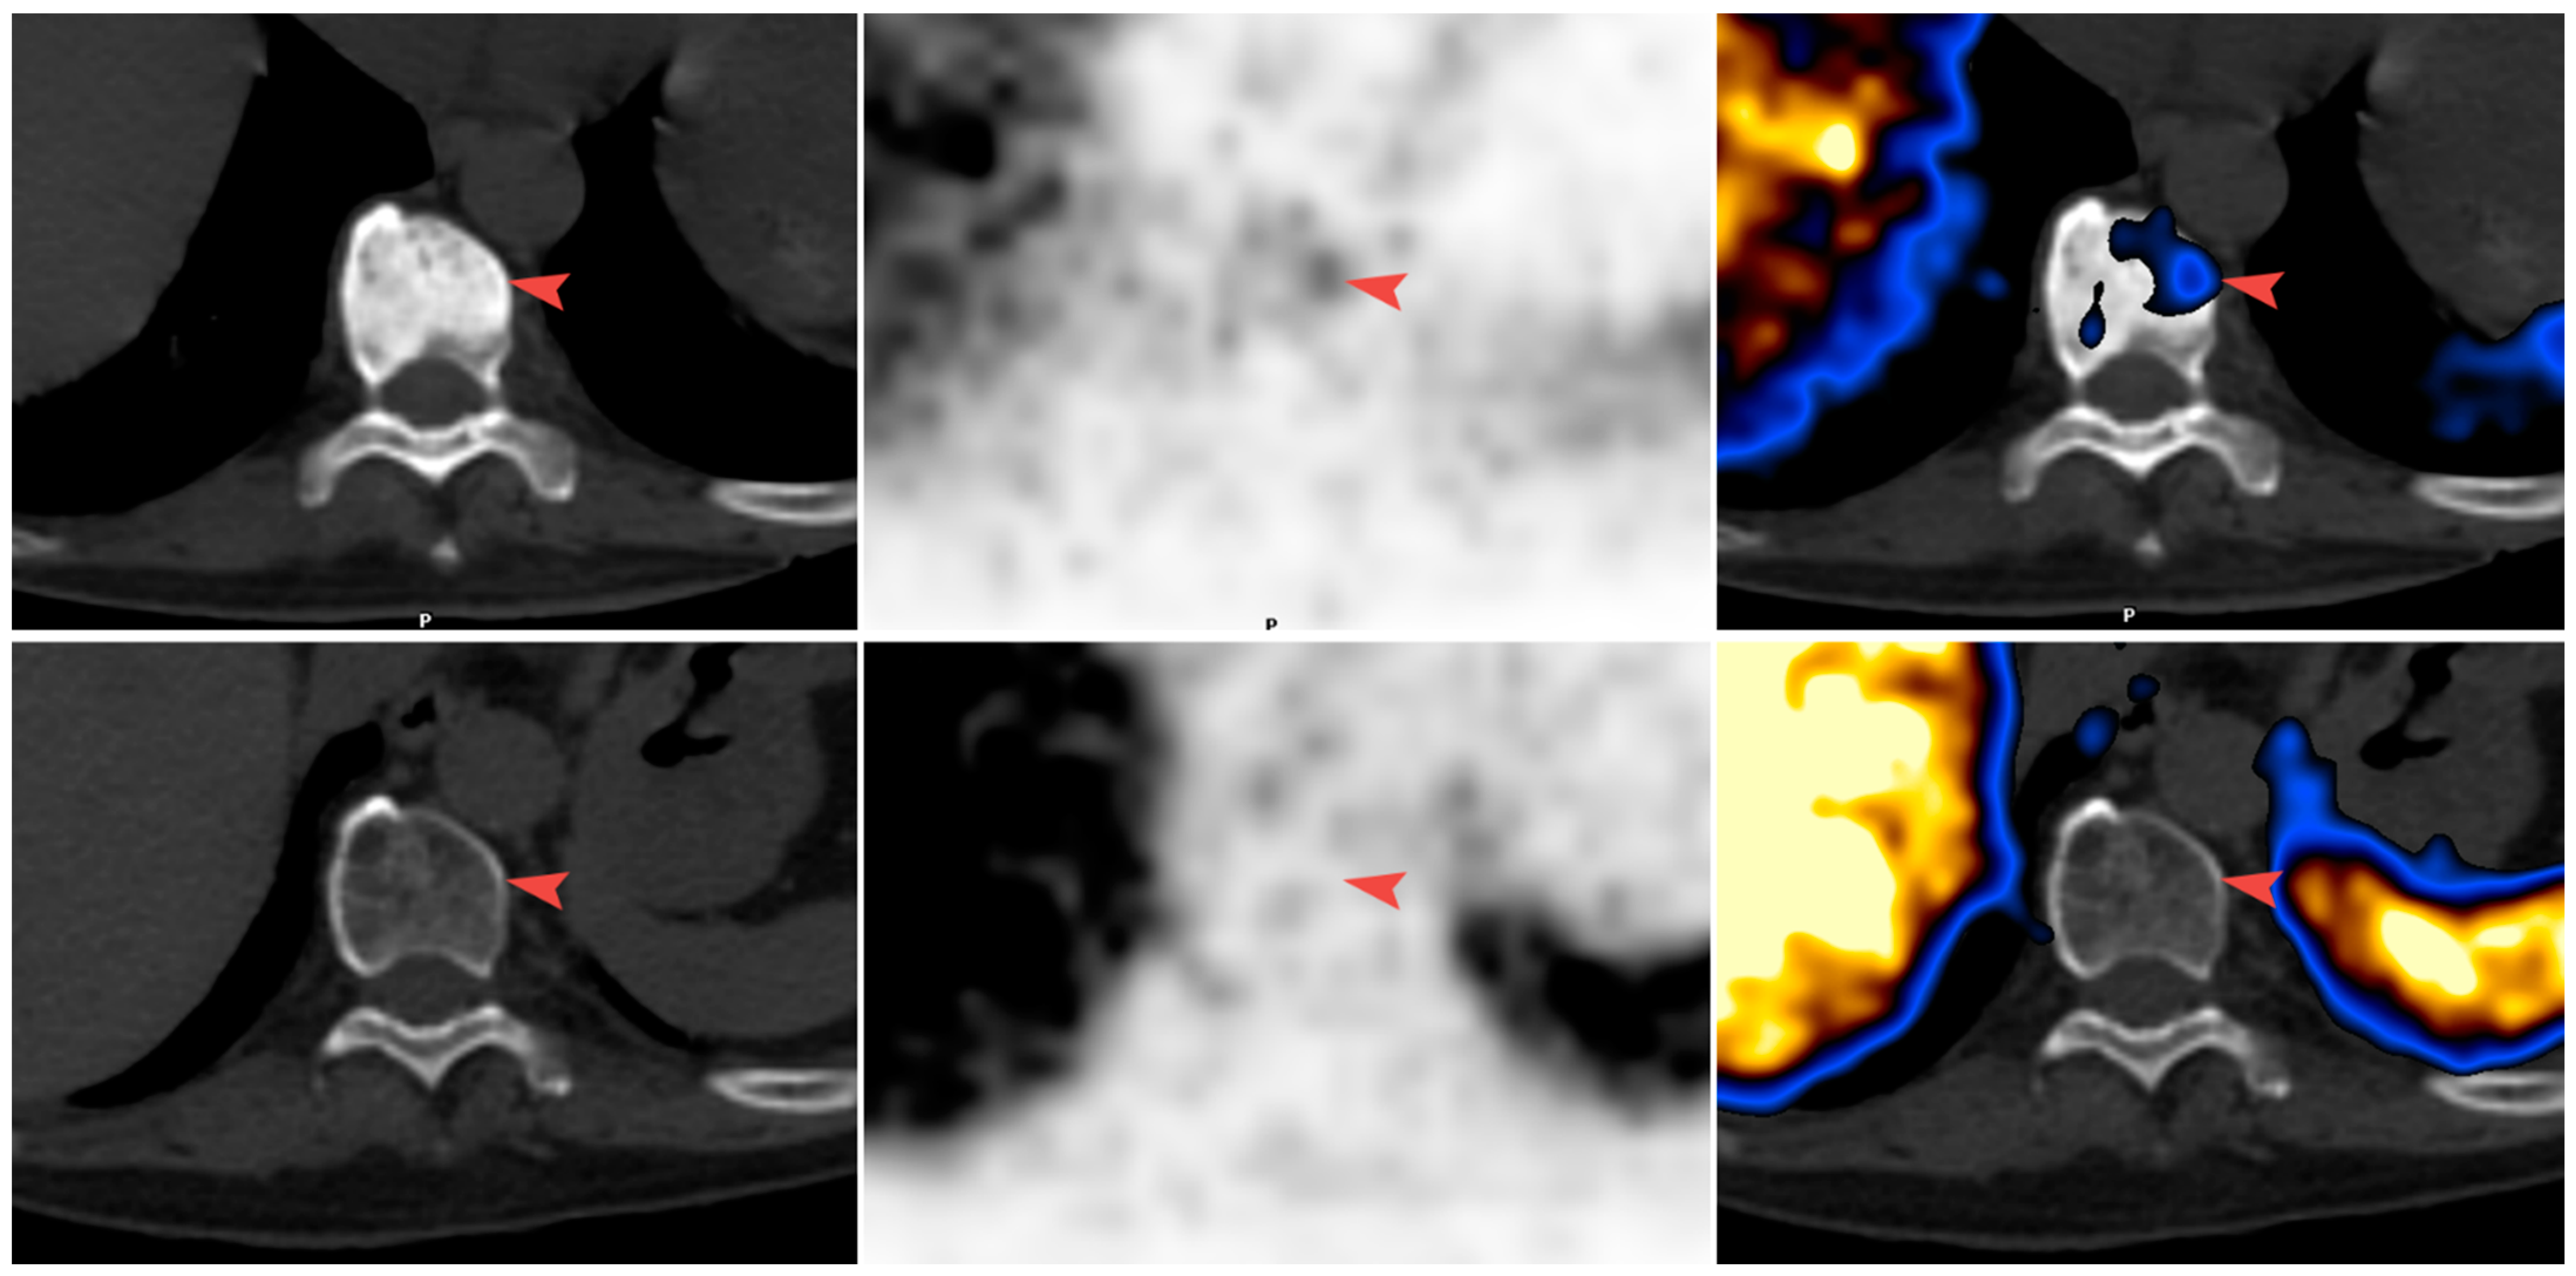

Figure 1 and Figure 2 illustrate bone metastases showing a reduction in bone density. Figure 1 illustrates a response. The reduction in bone density seen on the CT is associated with a reduction in tracer uptake on PET, while Figure 2 illustrates bone metastasis showing a reduction in bone density and positive PET, in keeping with active disease.

Figure 2.

Clinical progression (Patient 14). (From left to right) CT; PET; and fusion images. In the first scan after ADT, sclerotic metastases in the vertebra were identified in pelvic bones with very low uptake of 68Ga-PSMA-11 (arrowhead) (top row). In the second scan, the lesions were no longer sclerotic and showed intense 68Ga-PSMA-11 uptake (bottom row). PSA levels increased and a new metastasis was detected (arrow).